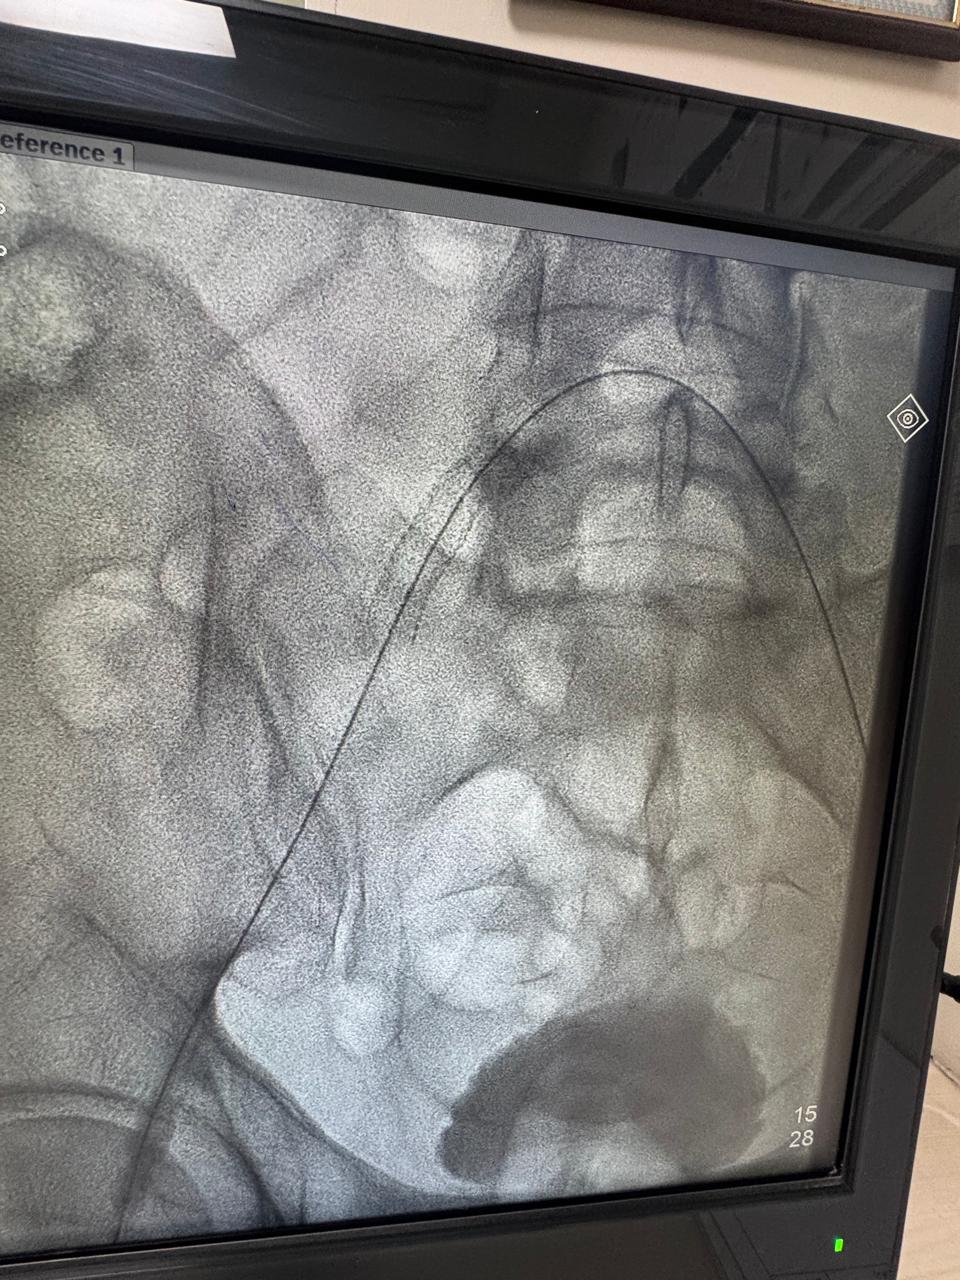

Critical stenosis in right iliac artery. Right iliac artery stenting done

Right leg critical ischemia grade 5 Hybrid treatment ( right iliac steering + angioplasty then femoro_popliteal bypass) done. Post -op ATA & PTA palpable confirmed on hand Doppler. Patient all symptoms subsides and walk normally.